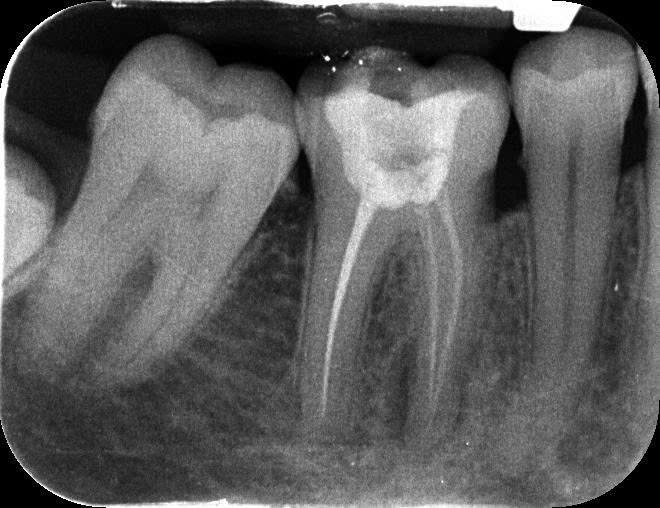

Прикладываю также прицельный снимок 46 зуба (в центре на центральном снимке) и 25 зуба (верхний левый второй премоляр, на прицельном снимке крайний слева) 7-месячной давности (27 февраля 2025 года).

Беспокоит 46 зуб (нижний моляр справа). Лет 15-20 назад запломбировали каналы.

Я проконсультировался у 2 разных докторов очно. Но так и не пришел к единому заключению. Я только понял, что есть апикальная инфекция у корня 46 зуба из-за прошлого некачественного лечения каналов.

По 46 зубу:

- Что делать с 46 зубом (перелечивать каналы или пока наблюдать, а если заболит, то удалять)?

- В каком состоянии корень 46 зуба? Выдержит ли он перелечивание каналов и возможно установку коронки?

- Откуда идет воспаление у 46 зуба: из каналов или со стороны десны?

- Если перелечивать каналы 46 зуба, то какой прогноз на перспективу?